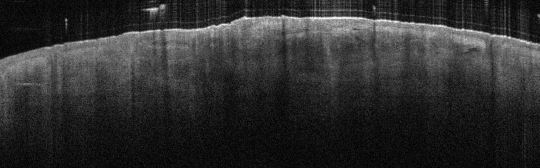

VA34: Right Temple, Actinic Keratosis, Hypotrophic, Focally reaching the base.

- White arrow denotes hair follicle

VA34: Right Temple, Adjacent, Normal

- Note normal hair follicle presentation